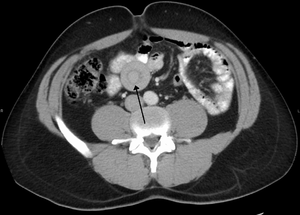

| An intussuception as seen on CT | |

An intussusception is a medical condition in which a part of the intestine invaginates (folds into) into another section of intestine, similar to the way the parts of a collapsible telescope retract into one another.[1] This can often result in an obstruction. The part that prolapses into the other is called the intussusceptum, and the part that receives it is called the intussuscepiens. Intussusception is a medical emergency and a patient should be seen immediately to reduce risk.

An intussusception is often suspected based on history and physical exam, including observation of Dance's sign. A digital rectal examination is particularly helpful in children, as part of the intussusceptum may be felt by the finger. A definite diagnosis often requires confirmation by diagnostic imaging modalities. Ultrasound is the imaging modality of choice for diagnosis and exclusion of intussusception, due to its high accuracy and lack of radiation. The appearance of target sign (also called "doughnut sign" on a sonograph, usually around 3 cm in diameter, confirms the diagnosis. The image seen on transverse sonography or computed tomography is that of a doughnut shape, created by the hyperechoic central core of bowel and mesentery surrounded by the hypoechoic outer edematous bowel.[7] In longitudinal imaging, intussusception resembles a sandwich.[7]